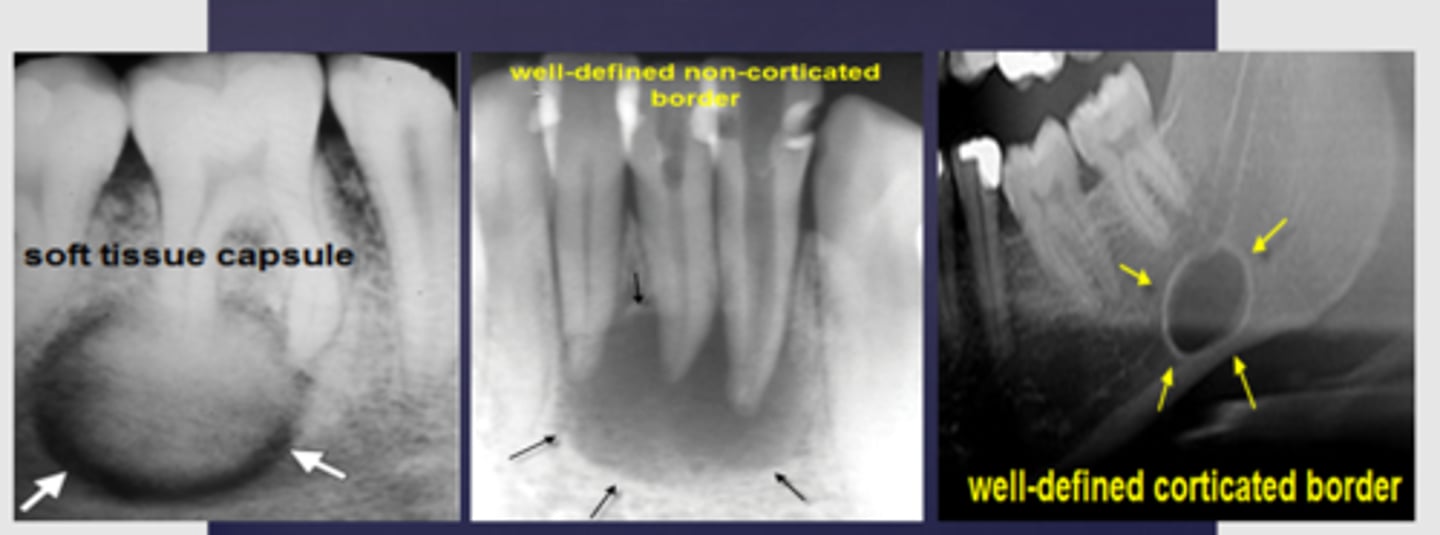

How is a radicular cyst described radiographically?

Well corticated

What characterizes non-corticated lesions?

Fast growing, nonvital teeth

What are unilocular radiolucent lesions?

Cysts, benign tumors